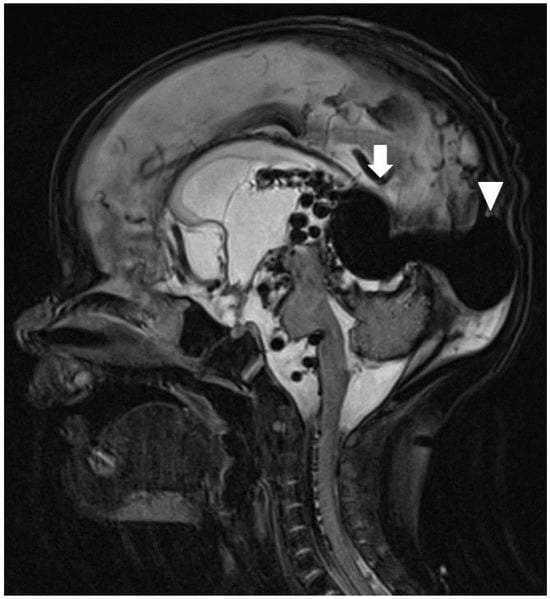

The patient was transferred to a tertiary paediatric hospital for paediatric neurosurgery and intervention radiology assessment, as this service was not available at our hospital. Following the transfer, a brain MRI was performed (Figure 3), and the patient underwent a coiling procedure to embolise the arterial feeders of the VGAM. In total, four coiling procedures were performed over a period of six weeks. Following the second of these, the patient was found to have hydrocephalus and underwent insertion of an external ventricular drain, which was removed after several weeks. Before discharge, an MRI of the brain demonstrated a reduction in the size of the VGAM and arterial collaterals, but also showed ongoing hydrocephalus and small bilateral infarcts in the corona radiata.

Figure 3.

T2-weighted sagittal MRI. The dilated galenic vein, namely, the median vein of prosencephalon (arrow), located midline in the cistern of velum interpositum, drains into the superior sagittal sinus (arrowhead).